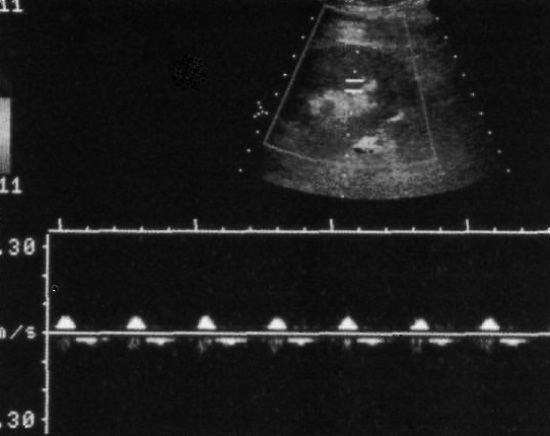

Фото 2. Трансплантат почки в норме. А – на продольном ультразвуковом изображении курсорами отмечен нормальный трансплантат почки – орган расположен непосредственно на поясничной мышце. Во время исследования измеряют длину и передне-задний размер органа. В – спектральная допплерография области нижнего полюса демонстрирует нормальный показатель индекса резистентности – 0,59. Нормальный поток и спектральные характеристики должны определяться над всей поверхностью трансплантата

Исключить очаговые инфаркты позволяет допплерография всей поверхности почки – определяют индекс резистентности над верхним и нижним полюсами, а также в средней области органа. Нужно оценить состояние кровотока в почечной и подвздошной артериях, почечной и подвздошной вене (фото 2-В).